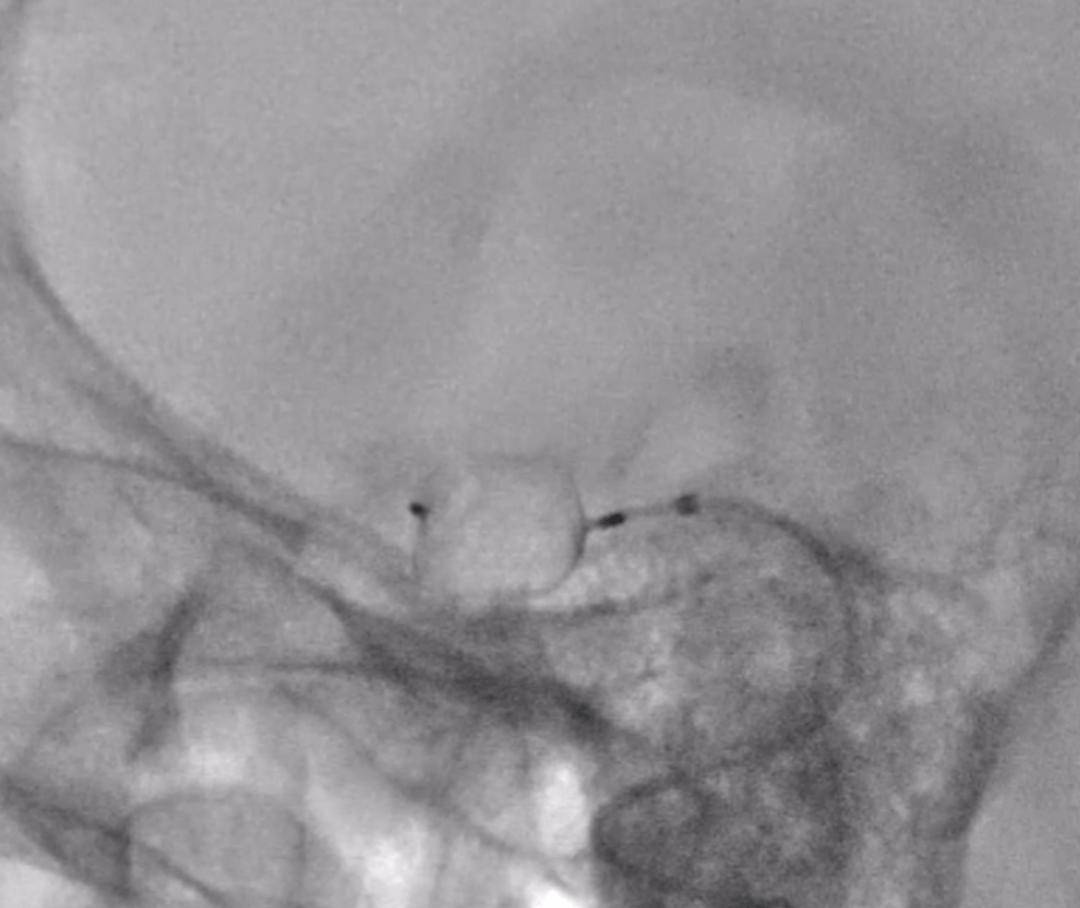

图5-7:扰流装置释放过程、释放结束、术后造影

术后造影显示:装置位置理想,动脉瘤内的血流动力学发生了预期的有利改变,而所有正常的脑血流未受影响。手术取得了圆满成功。